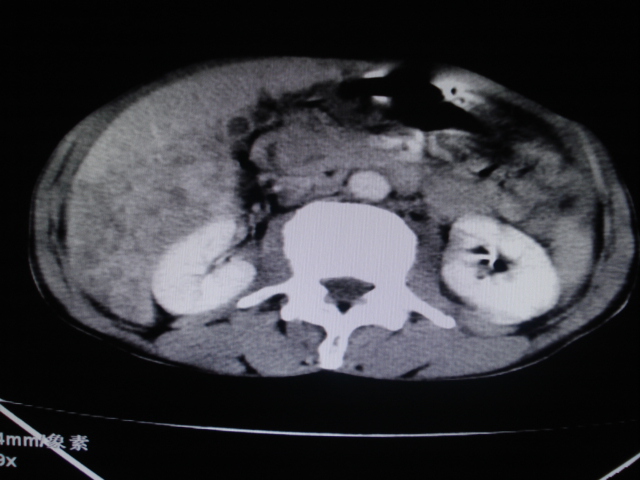

标题: CT24041:肝脏占位,请会诊!

男性,62岁。肝右叶占位,平扫及增强如下,延迟期为15分钟扫描。